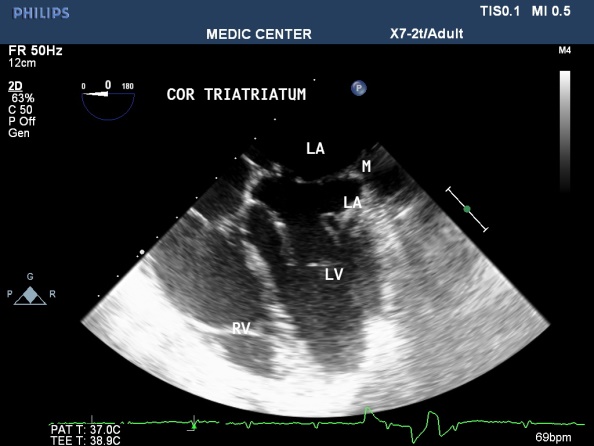

Figure 48. 2DTEE image with details of Cor Triatriatum

Figure 49. Live 3DTEE image showing Cor Triatriatum

Figure 50. Cor Triatriatum with aliasing flow through the separated membrane

Figure 51. Cor Triatriatum viewed from LA . a small opening of membrane noted